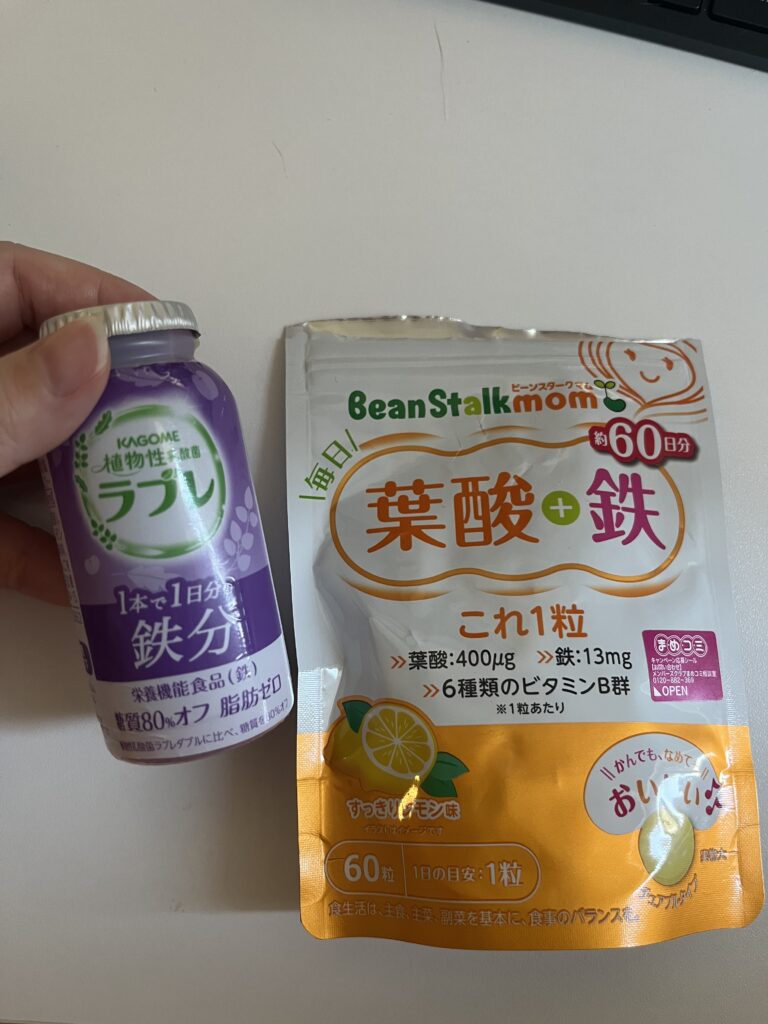

鉄分が足りないということで、ラブレという飲み物を追加しました。スーパーに売っています。妊娠前は鉄サプリをのんでいたのですが、それには妊婦が摂取してはいけないビタミンAが入っていたので飲めなくなっていました。

その代わりに葉酸と鉄のサプリを買ったのですがそれでは追いつかず、足のむずむずが止まりません。そこで「ラブレ」を追加してのんだらおさまりました。プルーンは妊婦が食べてはだめで、そのエキスが入っていますがチャッピーにきいたらこの程度だとOKとのことで飲んでいます。足のむずむずは眠れなくなるので、我慢は無理、解消していきたいです。